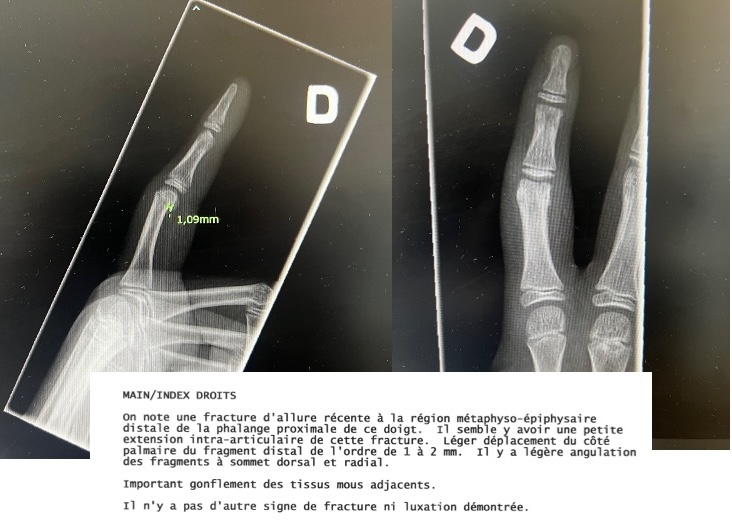

- Il y avait une blessure… et celle-ci était ÉVIDENTE ; l’enflure était si importante qu’elle a attiré l’attention de Coach Pascal, des arbitres et des autres joueurs.

Qu’est-ce qui a attiré l’attention de tout le monde ? Qu’ont-ils vu ?… Cela ! Voici à quoi ressemblait le doigt de mon fils…

Chacun pourra juger de l’état de la blessure et se demander : aurait‑on dû le laisser lancer dans ces conditions ?

L’index d’un enfant – abîmé, gonflé, fragile.

Le message cherche aussi à mettre en doute les photos :

« Pas sûr que la photo que tu as mise est celle avant son séjour au monticule… »

- Et si la fracture était survenue vendredi, le doigt aurait-il dû être parfaitement normal le dimanche ?

La radiographie serait-elle fausse elle aussi ?

Les images et la radiographie sont cohérentes, documentées et vérifiables.